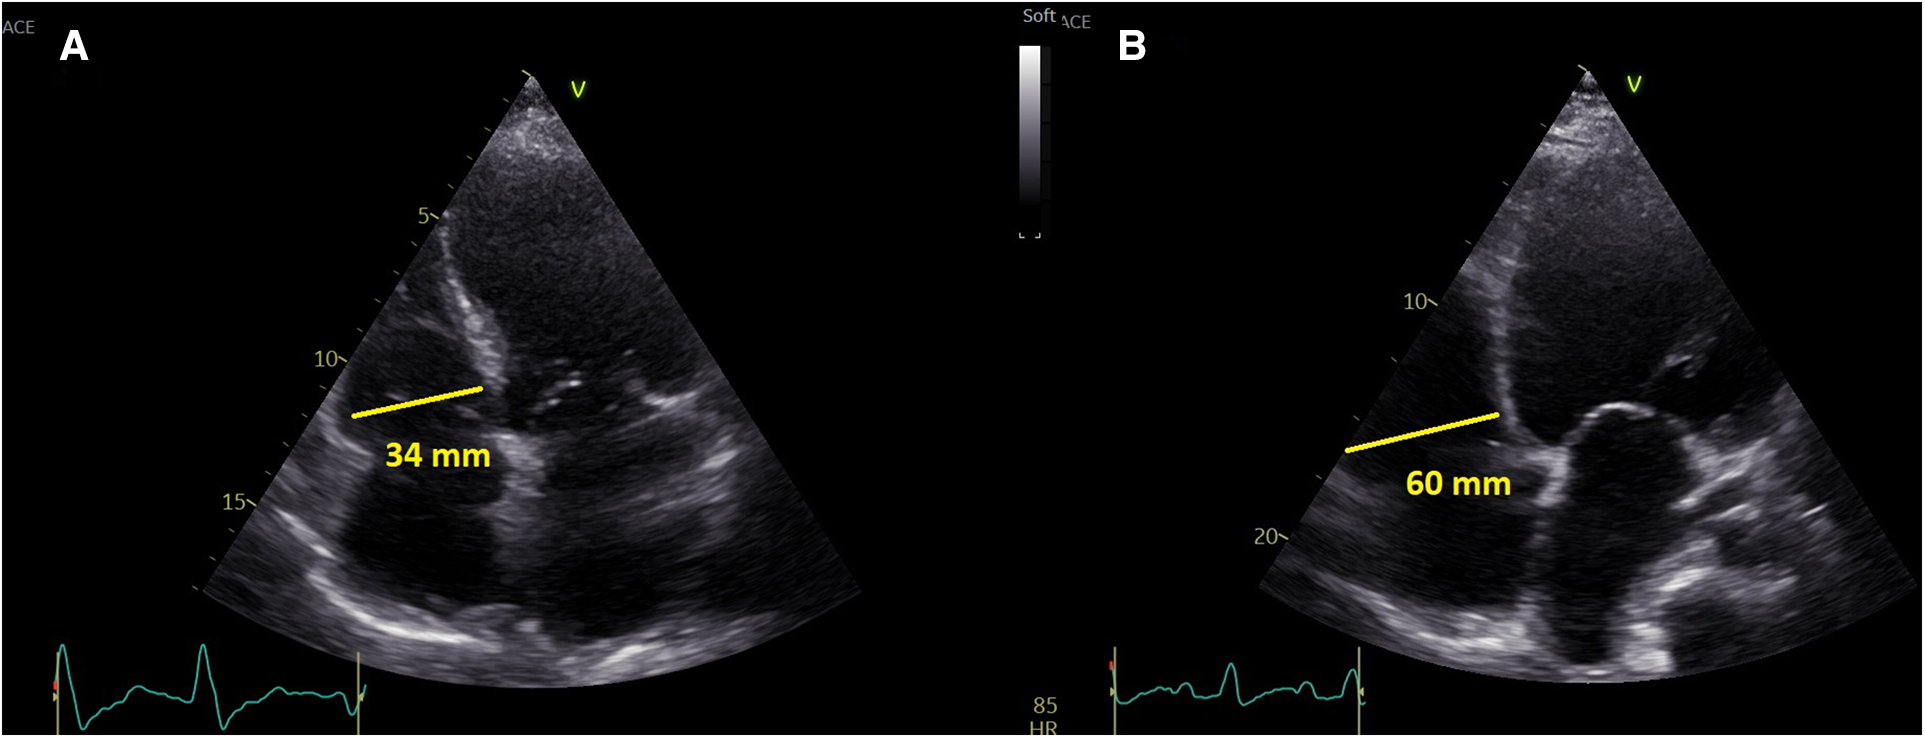

Left ventricular size was measured in parasternal long axis (PLAX) as end-diastolic diameter, LV ejection fraction was assessed by the Simpson method (10). Right ventricular size was measured in apical 4-chamber view (A4C) as RV-basal diameter (RVD1) (11). All sonographers were (as per institutional protocol) instructed to obtain the A4C projection with interventricular and interatrial septum perpendicular to the probe and to obtain the image of the “heart cross” with best available quality (Figure 1). RV dilatation was formally defined as RVD1 > 42 mm, but in the analysis it was used as a continuous variable.

Figure 1

A representative presentation of non-dilated right ventricle (left) and dilated right ventricle (right).